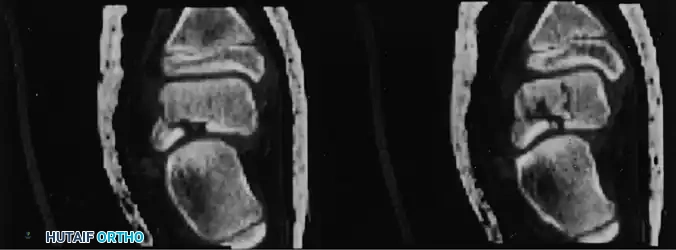

Standard radiographs often fail to accurately locate the lesion's anterior-to-posterior position. Computed Tomography (CT) in the coronal and axial planes is the gold standard for defining the exact location, size, and depth of the crater, which is critical for planning the surgical approach.

Fig. 33-207A Osteochondral lesion in anteromedial dome of talus. CT scan in axial plane shows crater and fragments.

Fig. 33-207B Coronal CT scan locates lesion whether anterior, middle, or posterior, which often is difficult to determine on radiograph.

High-resolution coronal CT demonstrating a deep medial osteochondral defect requiring surgical intervention.